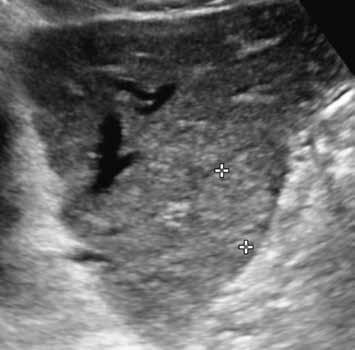

V UZ jsou patrná vícečetná izoechogenní ložiska (1, 2). U jiného pacienta (3) vidíme v játrech převážně hypoechogenní ložiska (žluté šipky) s naznačeným hyperechogenním periferním lemem (červené šipky). Po aplikaci kontrastní látky se ložiska patrná na obr. 1, 2 homogenně sytí a ani téměř po třech minutách nedochází k jejich vymývání (4–6).

Ultrazvukový obraz ukazuje většinou homogenní, někdy lobulované ložisko. V 60 % je hypoechogenní (obr. 1, 2), může však být izoechogenní nebo mírně hyperechogenní (obr. 3) vzhledem k normálnímu jaternímu parenchymu. Častěji se FNH vyskytuje v terénu steatotických jater. Ve 20 % případů nacházíme centrální jizvu.

V pravém laloku jater jsou na UZ lehce hypoechogenní ložiska s naznačeným výrazně hypoechogenním lemem (1, 2).